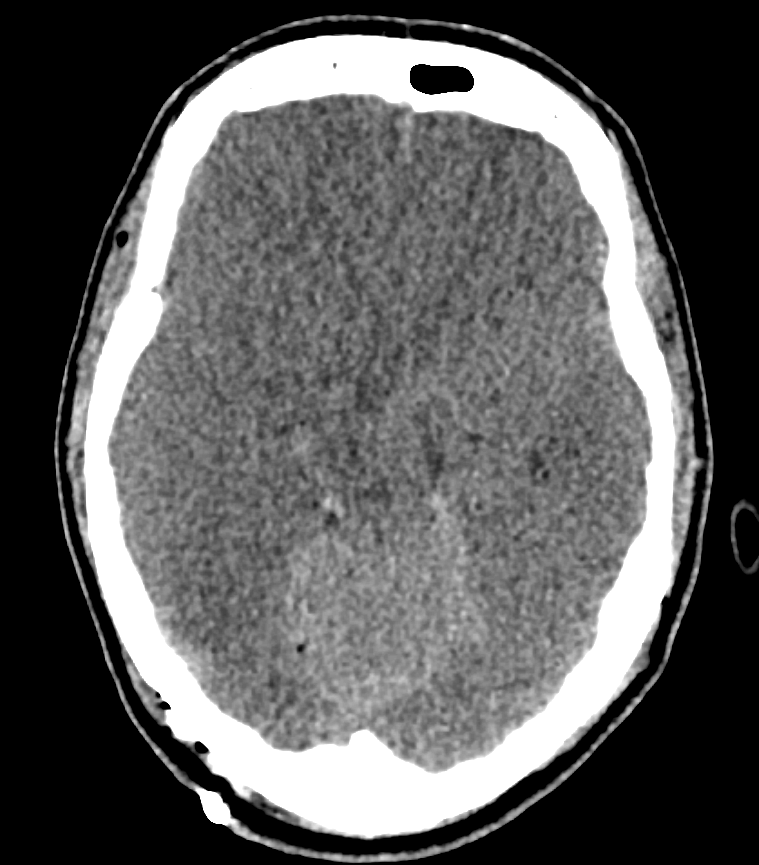

Axiales CT Bild eines Patienten mit einem generalisierten Hirnödem, verstrichenen Rinden-Markgrenzen und verstrichenen basalen Zisternen.